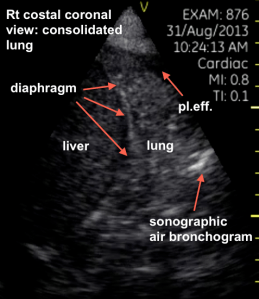

Right costal coronal view

Rt CCV labelled

The ultrasound diagnosis is of a consolidation with a small pleural effusion.  This can be referred to a “hepatization” as the appearance becomes quite similar to an unaerated organ. A sonographic air bronchogram is seen as well. Clinical correlation with the history and bloodwork strongly suggests a pneumonia.